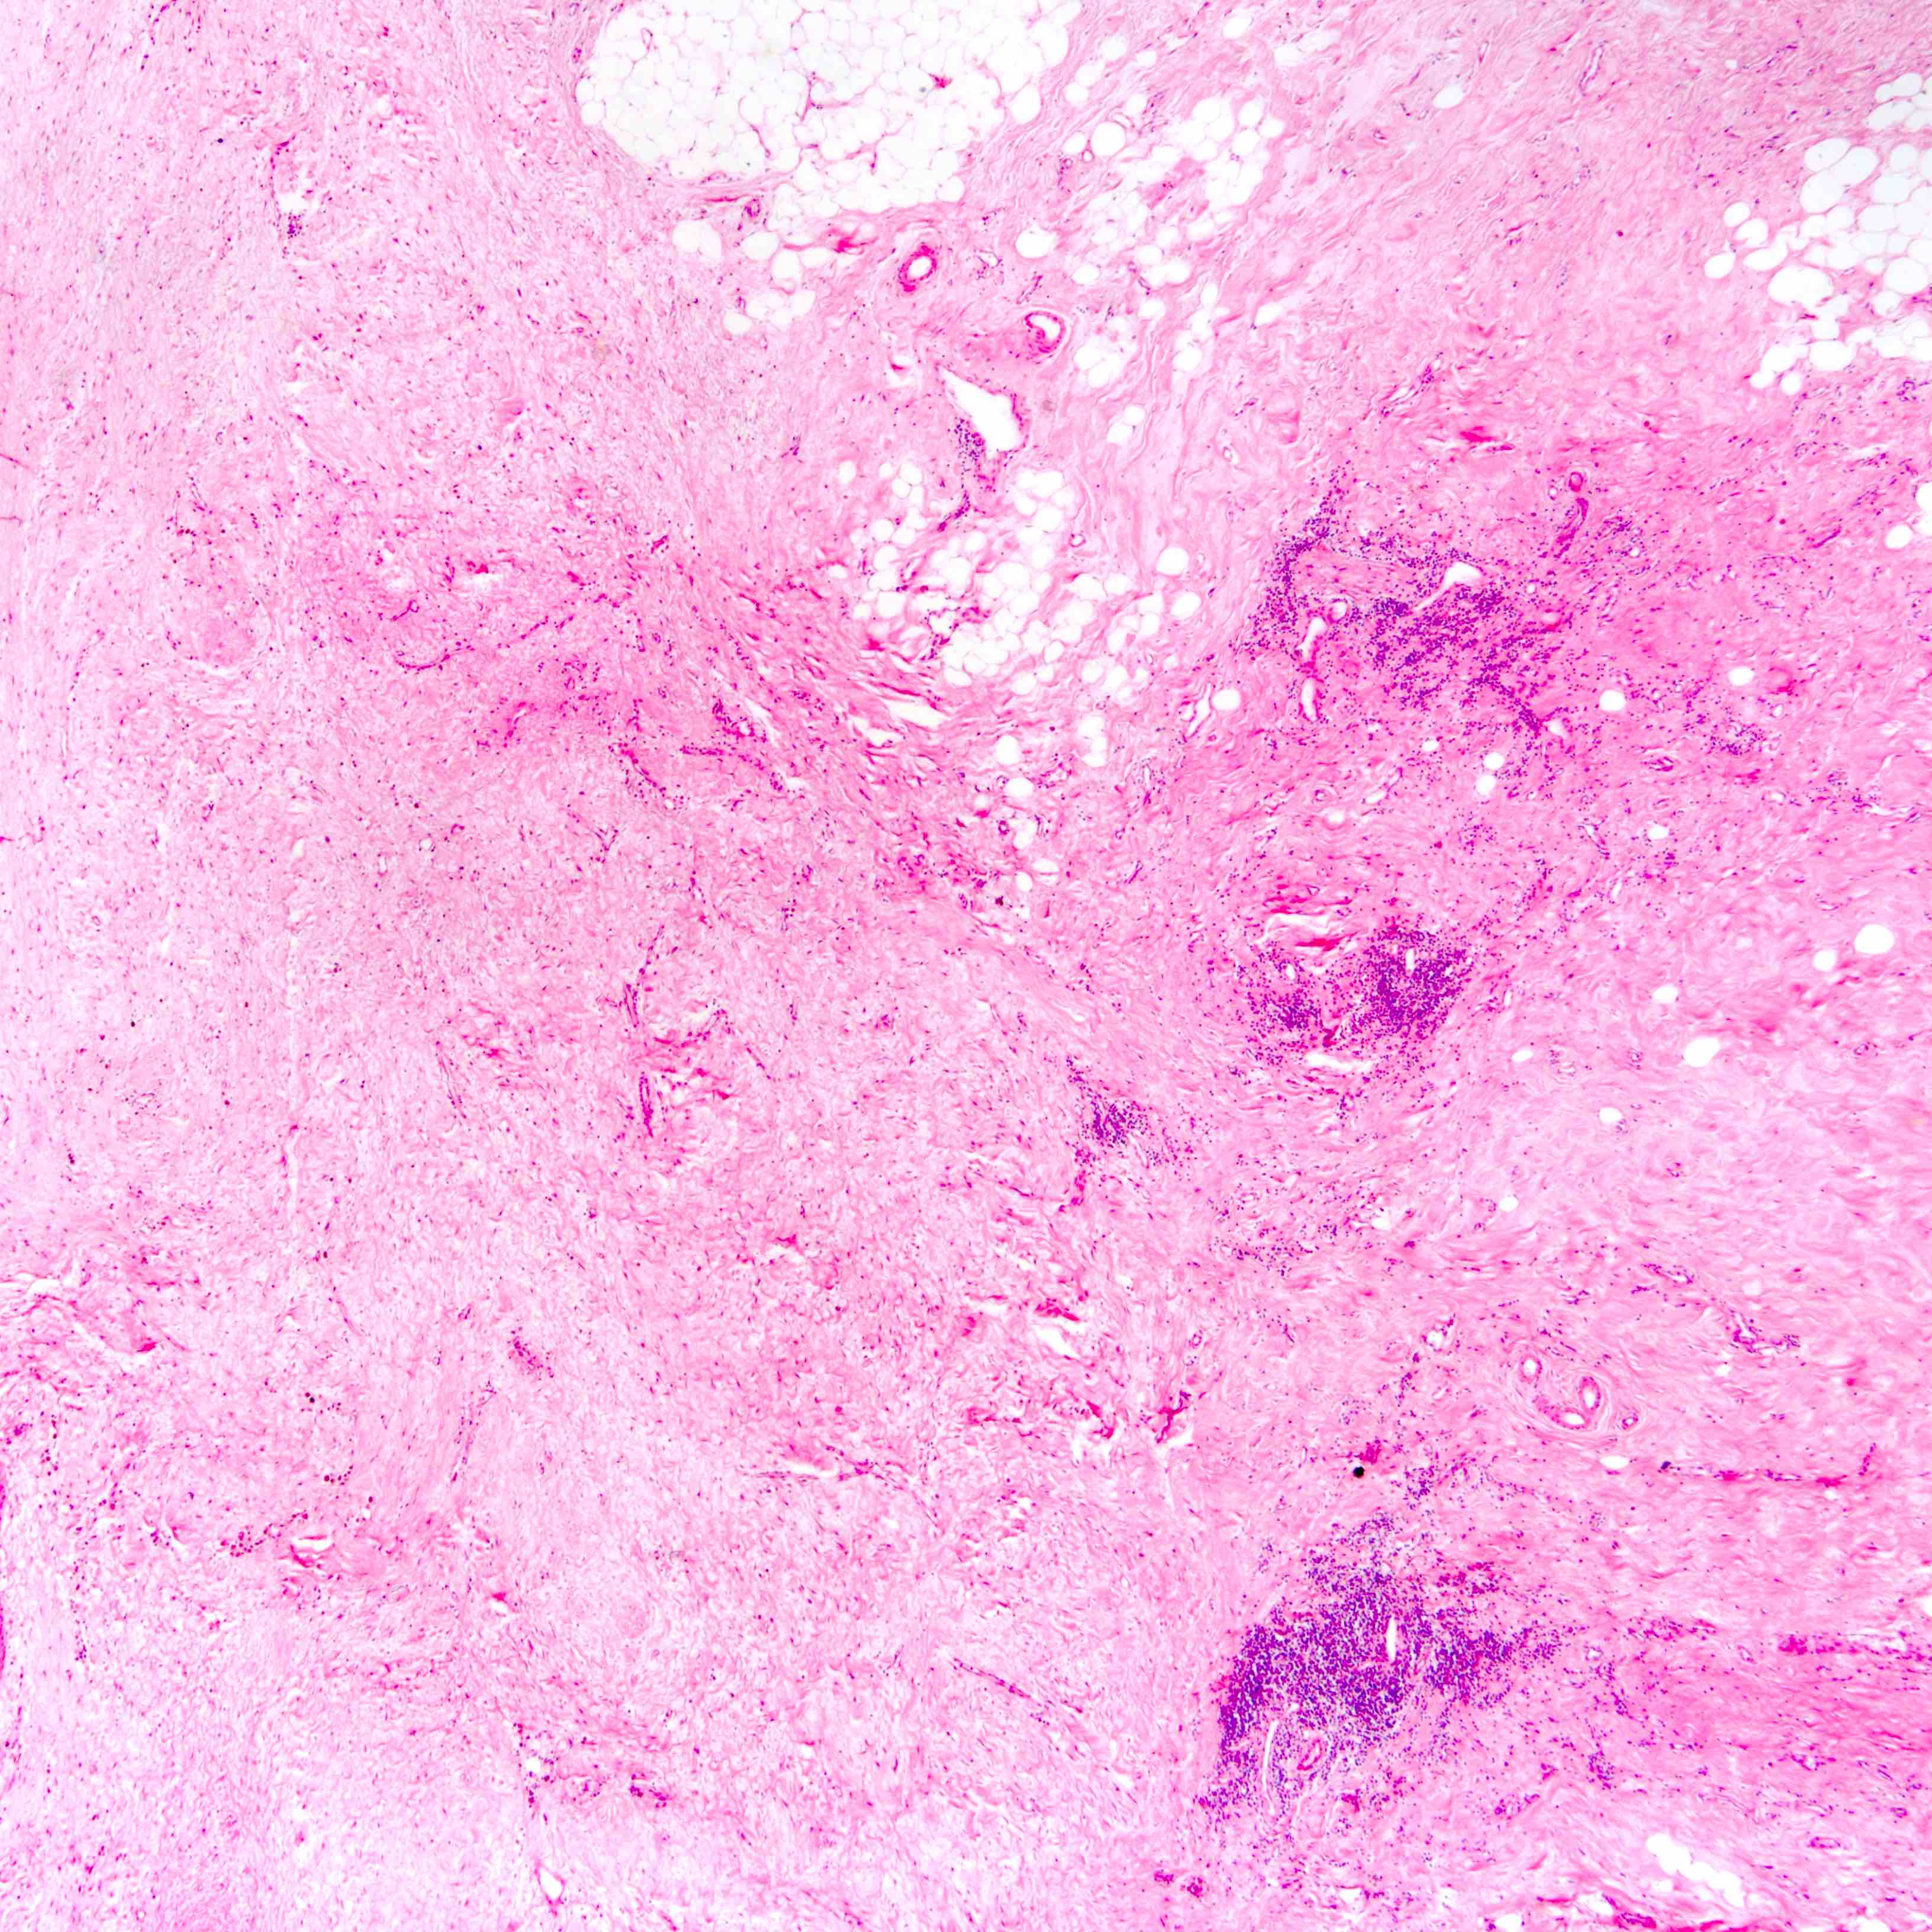

- Histologic evidence of tumor response includes fibrosis, hyalinization, lymphohistiocytic infiltration, hemosiderin laden macrophages, giant cell formation and vascular proliferation

- These histologic features are indicative of the tumor bed

- Patterns observed in partial response includes concentric tumor shrinkage, reduction in tumor cellularity and scattered multifocal tumor deposits (Mod Pathol 2015;28:1185)

- Normal breast tissue shows ductal and lobular atrophy, atypia and hyalinization of vessel wall

- Histological evidence of tumor response in the lymph node includes fibrosis, mucin pools, histiocytic infiltrates and lymphoid depletion

Microscopic (histologic) images

Contributed by Joshua J.X. Li, M.B.Ch.B., Gary M. Tse, M.B.B.S. and Emily S. Reisenbichler, M.D.